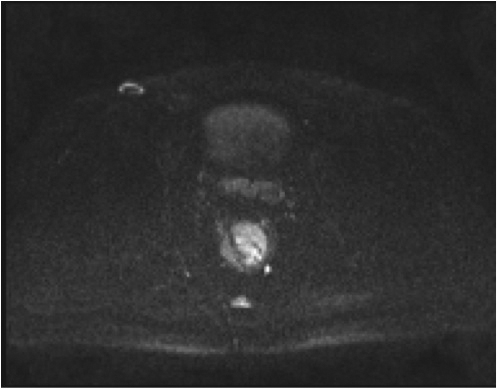

Fig.2. Același pacient post chimio-/ radioterapie – răspuns complet cu dispariția masei tumorale rectale; dispariția restricției de difuzie și reducere în dimensiuni a ganglionilor mezorectali; pacientul a beneficiat de TME şi s-a confirmat histopatologic absenţa ţesutului tumoral (pT0 pN0).

a-d) imagini T2 ponderate în 3 planuri

e) difuzie RM (b1000)

f) sagital T1 postcontrast